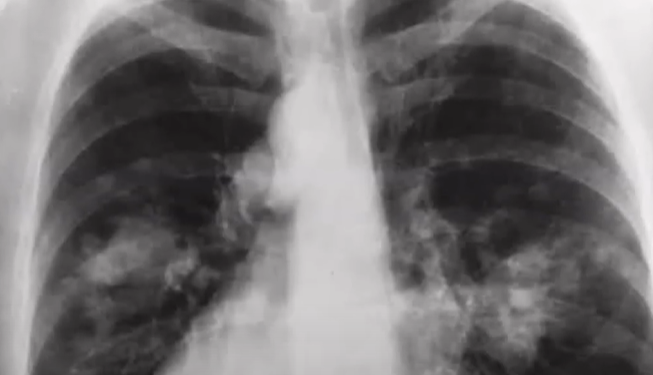

סרטן הריאות זכה זה מכבר לתואר המפוקפק "הסרטן הקטלני בעולם" ובישראל הוא סוג הסרטן הקטלני ביותר הן בקרב גברים והן בקרב נשים. על פי הערכת האגודה למלחמה בסרטן, עד סוף שנת 2024 יאובחנו בישראל כ-2,900 נשים וגברים עם סרטן הריאות וכ-1,800 ככל הנראה ימותו מהמחלה. על פי סקר שערכה האגודה למלחמה בסרטן בשיתוף חברת מחקרי השוק הבינלאומית Ipsos, כשליש מהציבור מכיר מישהו שהונע להתחלה או חזרה לעישון במהלך שנת 2024, כמחציתם קשורים לשירות הצבאי. אירועי ה-7 באוקטובר היוו גורם לחץ משמעותי שדחף לעלייה בהרגלי העישון של כ-33 אחוזים מכלל המעשנים: 12 אחוזים חזרו לעשן, 21 אחוזים מעשנים יותר. מאידך, רק 7 אחוזים הפסיקו לעשן במהלך שנת 2024, כאשר לפי האגודה אדם שמפסיק לעשן מפחית באופן משמעותי את הסיכון שלו לחלות ואפילו אדם שמפסיק לעשן לאחר שאובחן כחולה סרטן מגביר בכך את סיכויי החלמתו.

מומחי האגודה למלחמה בסרטן מדגישים כי אם אחד מהתסמינים המפורטים לעיל נמשכים למעלה משלושה שבועות, חשוב להיבדק על ידי רופא משפחה. כל התסמינים עלולים להיגרם גם מעישון או ממחלות אחרות שאינן סרטן. לעיתים סרטן ריאות מאובחן באופן אקראי באנשים שאינם סובלים מתסמינים כלל, אך נבדקים בצילום או בסריקת ריאות לבירור בעיה אחרת.